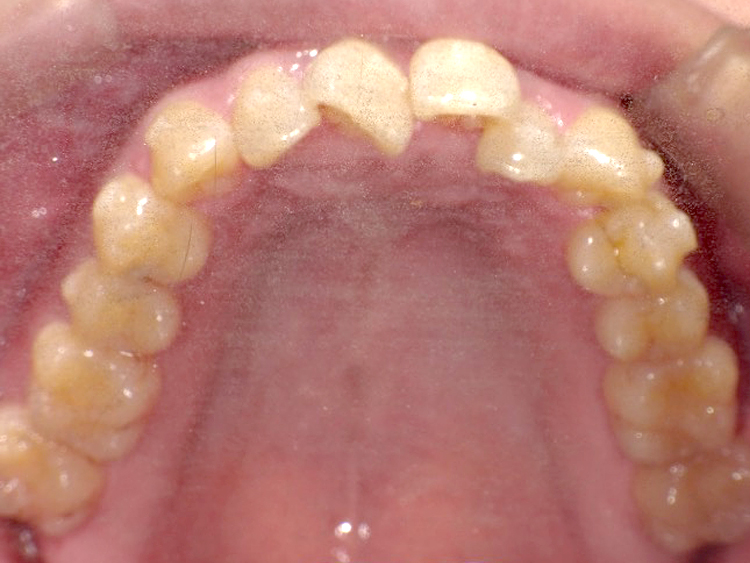

症例3

Before

After

| 主訴 | 上下の歯のガタガタを治したい |

|---|---|

| 年齢 | --- |

| 治療期間 | 約10ヶ月 |

| 治療内容 | インビザラインiGoで上下顎の治療。 狭まっていた歯並びを広げることで、 ガタガタに並んでいた歯を綺麗に並べた。 |

| 治療費 | ¥517,000(税込)+月額調整料 |

| 治療のリスク | 歯と歯の間を削ることでスペースを確保するので、 場合によっては歯が染みる症状が出ることがある。 |